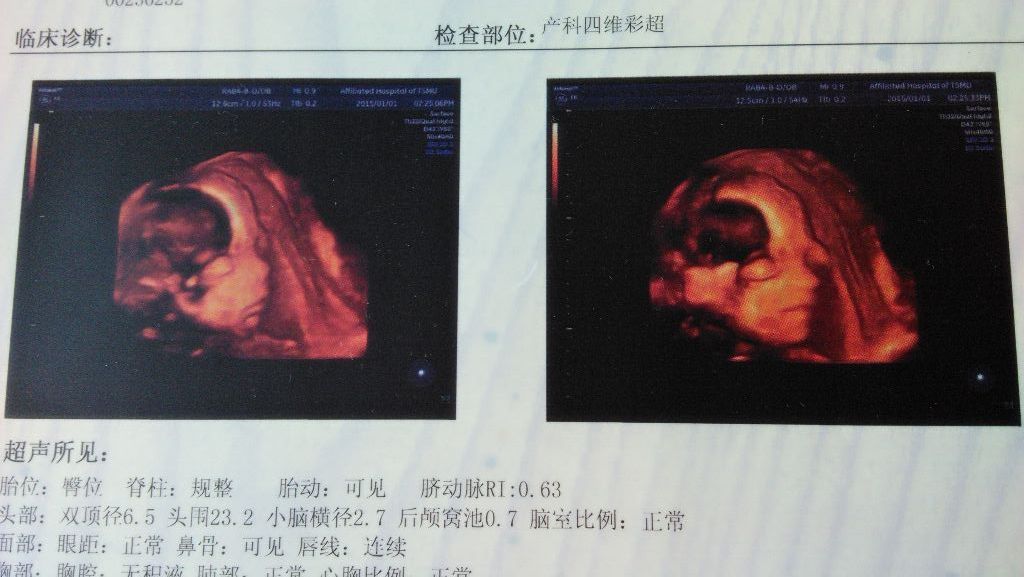

有懂产科的吗,帮我看看四维彩超可以吗 前几天刚做了四维,宝宝脑袋那有一大块黑乎乎的地方,也不知道是什么部位,脸上有两个地方有黑色的暗区,怕是胎记,能帮我看看嘛,当时没来得及问医生 点击展开 匿名用户 2015-01-04 10:50 为您推荐: 其他回答 你好,宝宝脑袋上的黑呼呼的地方是在采集图像的时候有胎盘或宫壁遮挡形成的,不是胎记, 天使7737 2015-01-04 20:36 相关问题 什么四维彩超我根本就看不懂,有谁能帮我看看? 求助:麻烦懂产科的宝妈帮我看看! 各位,能不能帮我看看什么意思啊,不懂,还有能不能判断有几周了???谢谢啦